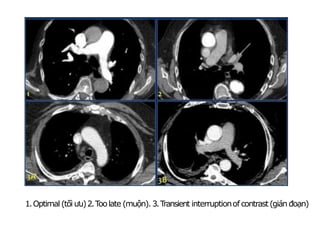

1.Optimal (tối ưu)2.T

oolate (muộn). 3.T

ransient interruptionof contrast(gián đoạn)

Transient Interruption of Contrast: Deep inspiration results in dilution of

contrast in the right atrium by unopacified blood from the inferior vena

cava. (Gián đoạn thuốc tương phản)